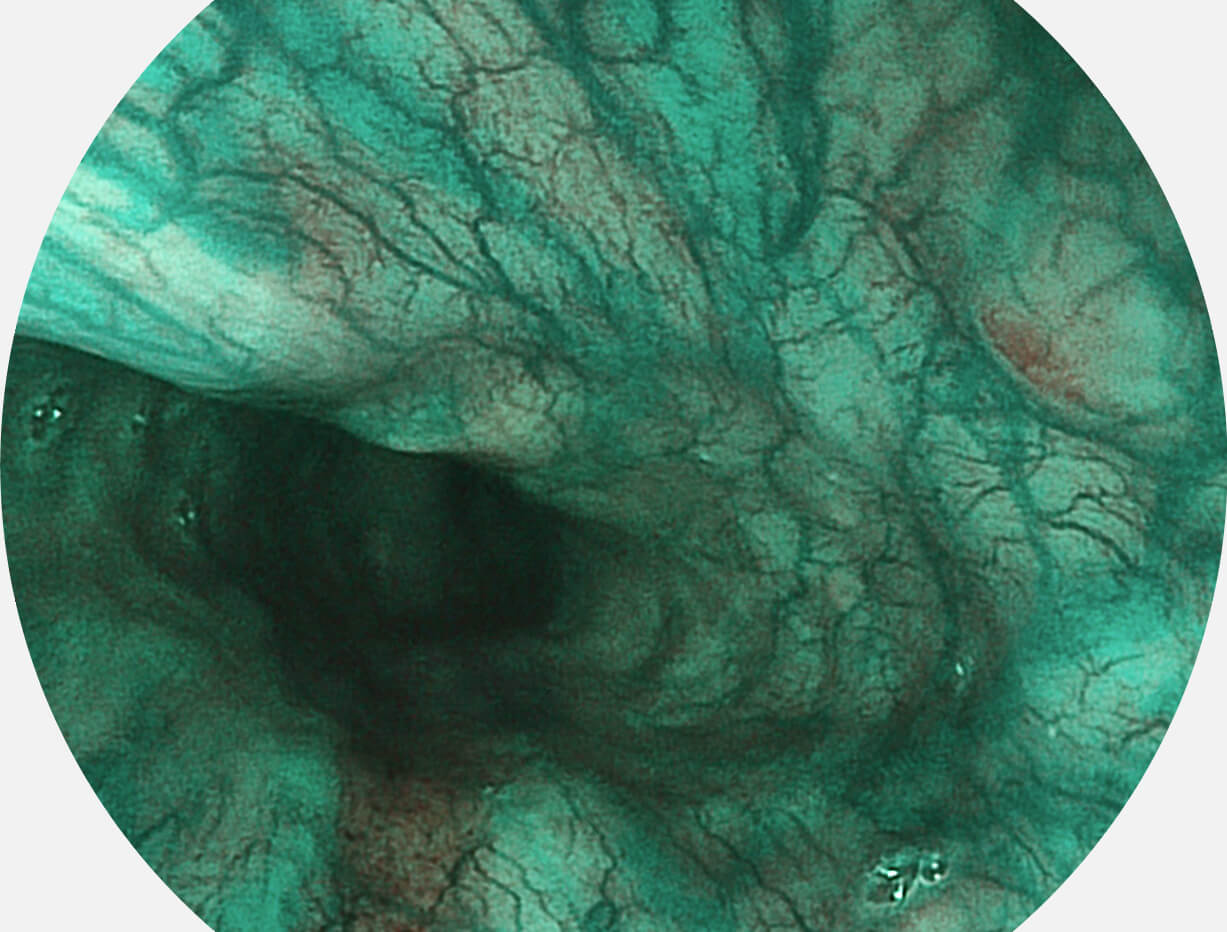

白光图像

VIST图像